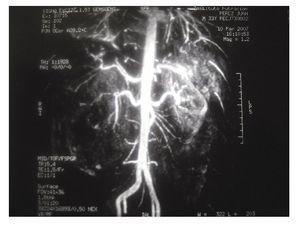

Una vez en mejor estado general se realizó tomografía axial computarizada que mostró una imagen de un tumor renal derecho de 10 UH heterogéneo que desplazaba en sentido posteroinferior y medial al riñón (Imagen 1). Las dimensiones del tumor fueron de 15 cm en sentido longitudinal y 10 cm en sentido transversal, de características heterogéneas con un refuerzo de -30 UH al administrar medio de contraste, lo que aumentó la sospecha de angiomiolipoma renal. Se realizó resonancia magnética con reconstrucción vascular, en la cual se observó hiperintensidad en T1, isointensidad en T2, sin delimitar el tumor y con sangrado con dimensión aproximada de 6-7 cm de diámetro (Imagen 2). En la angiorresonancia se observó pobre vasculatura, incrementando la sensibilidad diagnóstica para angiomiolipoma (Imagen 3).

Imagen 3. Angiorresonancia.